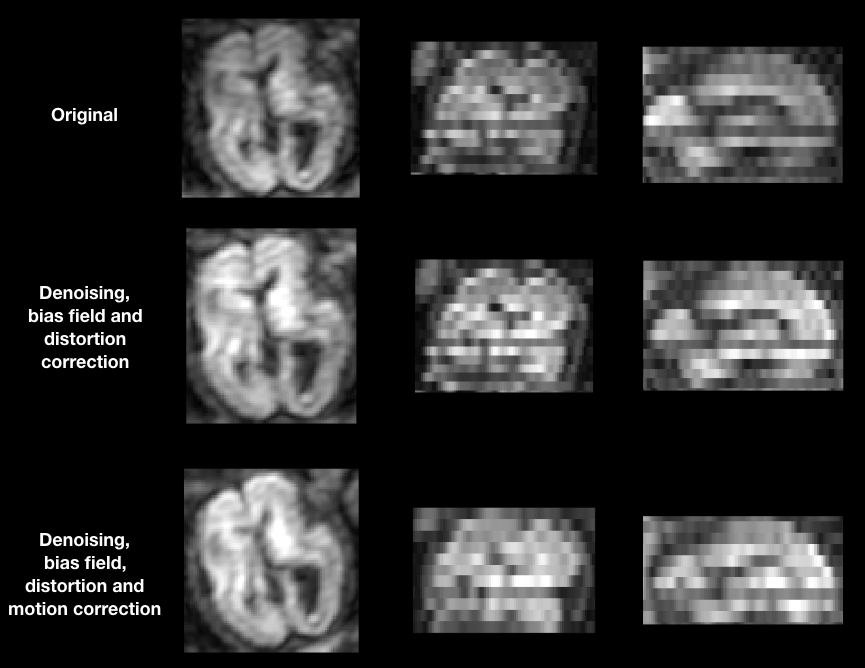

We selected three subjects with high quality imaging and without motion artifacts (24, 29, and 35 GW) and three subjects with a varying degree of motion (23, 24, and 27 GW). Supplementary Figure S1 shows the distribution of gestational age of both 31 pre-term newborns and the 6 fetal subjects used in this study. A DW-MRI volume of a motion-free case (Sub-2, 29 GW) and a pre-term of equivalent age are illustrated in Figure 1. By performing quality control, we discarded highly corrupted volumes due to motion resulting in severe signal drops in two moving subjects and very low SNR volumes in one motion-free subject. Table 2 presents the different characteristics of each subject as well as its corresponding discarded volumes. The coronal volume was not used to avoid any interpolation confounding factor while co-registering different orientations. All the subjects were pre-processed for noise, bias field inhomogeneities, and distortions using the Nipype framework (46). The denoising was performed using a Principal Component Analysis based method (47), followed by an N4 bias-field inhomogeneity correction (48). Distortion was corrected using an in-house implementation of a state-of-the-art algorithm for the fetal brain (14) consisting in rigid registration (49) of a structural T2-weighted image to the b0 image, followed by a non-linear registration (49) in the phase-encoding direction of the b0 to the same T2-weighted image. The transformation was then applied to the diffusion-weighted volumes. A block matching algorithm for symmetric global registration was also performed for two subjects (sub-4, sub-6) with motion [NiftyReg, (50)]. The b0 image of the first axial series was selected as a reference to which we subsequently registered the remaining volumes, i.e., the non b0 images from the first axial and all volumes from the two others. Gradient directions were rotated accordingly. Supplementary Figure S2 shows an example of a DWI volume (from sub-4) of original, pre-processing, and motion correction.

Figure 1. Illustration of the three orientations of a Diffusion weighted-magnetic resonance imaging (DW-MRI) volume from a still fetal subject (29 GW) and pre-term newborn of the same gestational age.